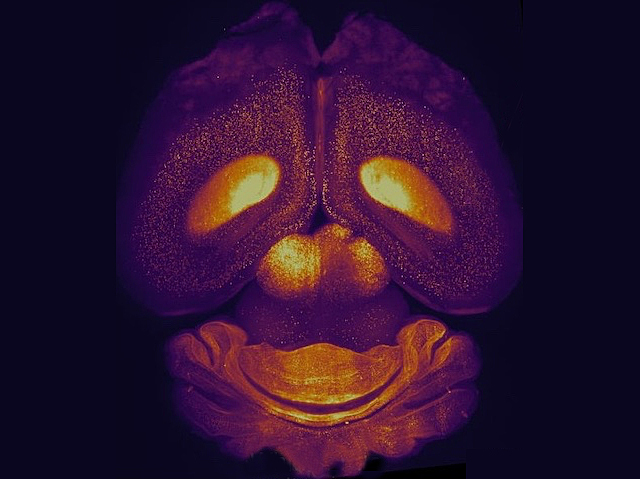

Of Your Gourd

A novel self-supervised learning approach called CellSeg3D for fluorescence microscopy (data from a whole human brain shown) to quantify cells in 3D volumes, such as in cleared tissue